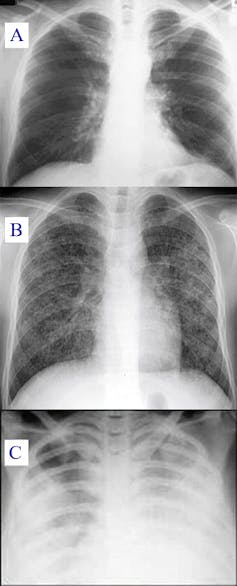

Une radiographie des poumons, ou un scanner si nécessaire, permet au médecin de mesurer l’étendue de l’atteinte pulmonaire. Il s’appuie également sur des examens biologiques complémentaires (gaz du sang) afin d’évaluer le degré de l’atteinte, et son retentissement sur les autres organes. Enfin, comme dans toute infection respiratoire virale, des analyses sont menées pour détecter une éventuelle co-infection bactérienne. La « collaboration » entre virus et bactéries, qui aggrave leurs pouvoirs pathogènes respectifs, est en effet fréquente.